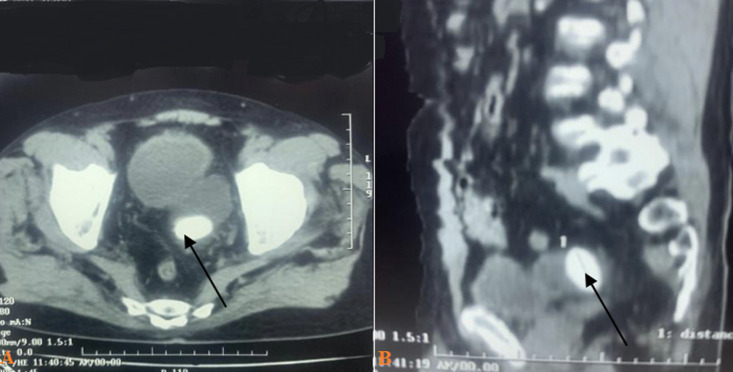

结石的形成可能是由于膀胱憩室的尿液淤积所致。然而,结石通常体积较小,可以自行排出。然而,膀胱憩室内的巨大结石被认为是罕见的实体。我们报告一位69岁男性,有两年的下尿路症状史,并伴有尿路感染复发。腹部计算机断层扫描显示存在巨大膀胱憩室和大膀胱结石。患者接受经尿道膀胱颈部切口,随后行憩室切除术并取出结石。憩室尺寸为6x4x3.8厘米,憩室结石尺寸为4x3x3厘米。幸运的是,病人手术后恢复得很好。综上所述,大膀胱憩室内的巨大结石是罕见的,在有下尿路症状的患者中应予以考虑。早期诊断和最佳处理是预防长期并发症的原则。

The stone formation could occur due to urine stasis in the bladder diverticulum. However, the stones are usually smaller in size and can pass spontaneously. However, a giant stone inside vesical diverticulum is considered a rare entity. We report a 69-year-old male, with a two-year history of lower urinary tract symptoms along with a recurrence of urinary tract infection. An abdominal computed tomography scan revealed the presence of a giant bladder diverticulum and a large bladder stone. The patient underwent a transurethral bladder neck incision followed by diverticulectomy with stone extraction. The diverticulum size measures 6x4x3.8 cm and diverticulum stone size of 4x3x3 cm. Fortunately, the patient recovered well after the operation. In conclusion, giant stones inside large vesical diverticulum are a rare occurrence and should be considered in patients with lower urinary tract symptoms. Early diagnosis and optimal management of the obstruction are the principles to prevent long-term complications.